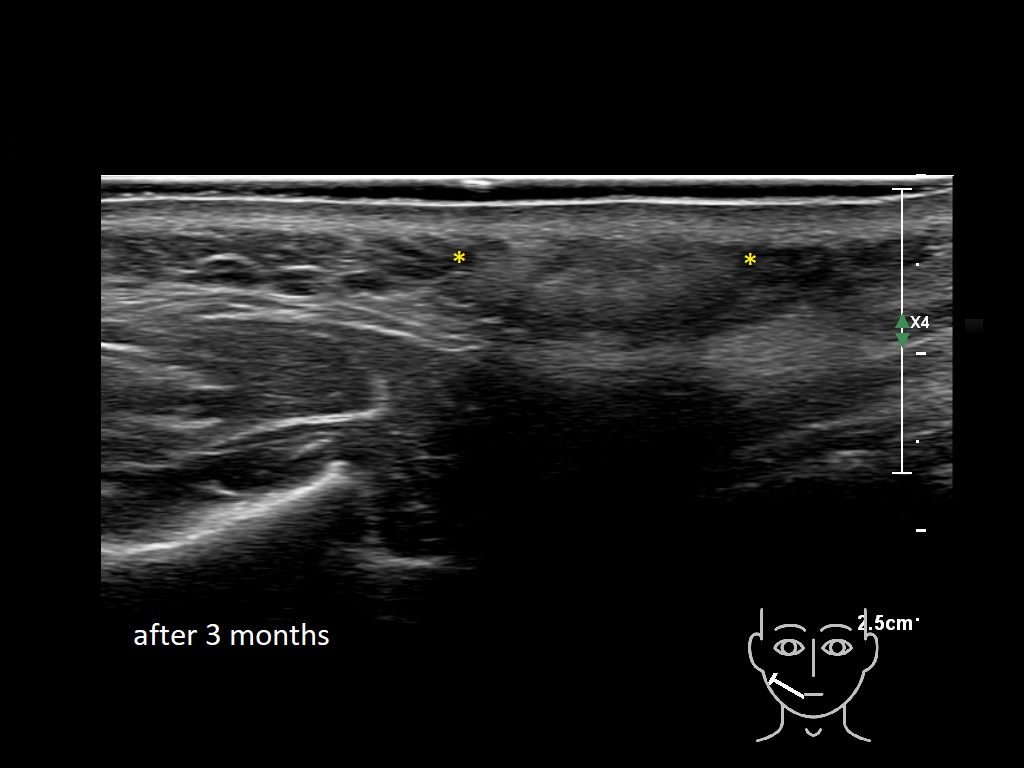

Draw in the image on the right where the fillers are located. To check if your answer is correct, please click on the secondary image.

Fillers

Draw in the second image below where the fillers are located. To check if your answer is correct, swipe the first image to the right.